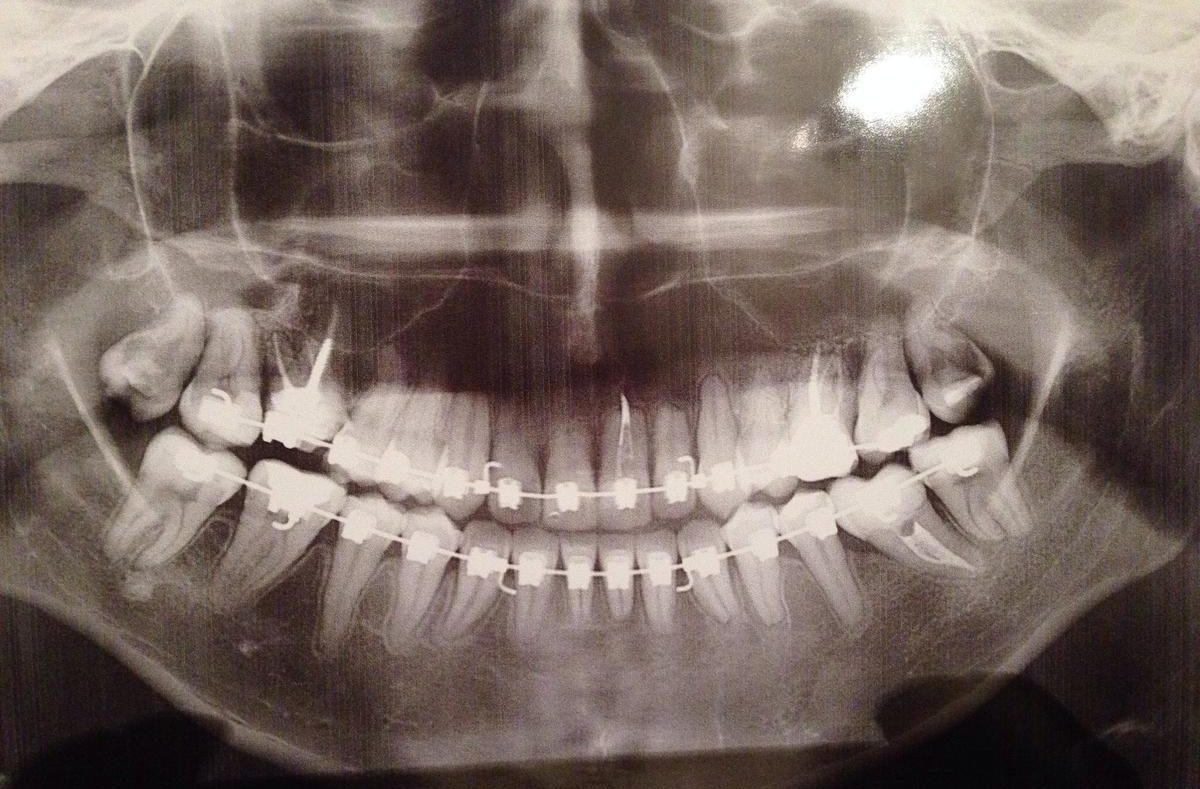

Примеры ортопантомограмм и их анатомия

Раздел: Фотоэссе